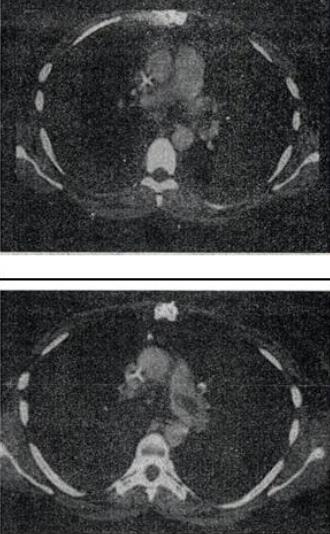

患者女,51岁,心脏手术后,突感胸痛,结合CT图像,最可能的诊断是()。

A、肺栓塞

B、支气管扩张

C、肺水肿

D、肺癌

E、肺不张

A